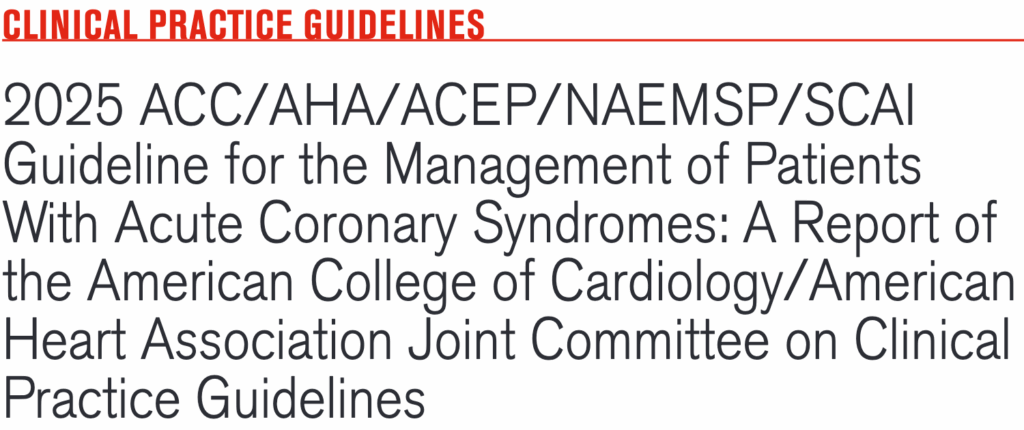

La guía 2025 para el manejo de los Síndromes Coronarios Agudos de la ACC/AHA/ACEP/NAEMSP/SCAI1 menciona que los pacientes que se presentan con Infarto Agudo del Miocardio (IAM) y FEVI <40% tienen riesgo incrementado de presentar Fibrilación Auricular de nuevo inicio, bradiarritmias (como en esta paciente) y arritmias ventriculares. Esto incrementa en los pacientes que no reciben alguna estrategia de reperfusión, sea fibrinolisis o Intervencionismo Coronario Percutáneo (ICP).

Pues bien, para las bradiarritmias en el contexto de IAM, la guía 2025 nos dice que la colocación de un marcapasos permanente está indicada. Y eso fue lo que buscamos hacer tan pronto arribó la paciente y, aun en la camilla de la ambulancia, la acercamos al monitor desfibrilador de nuestra área de reanimación, presentando a los pocos segundos crisis convulsivas asociadas a una frecuencia cardíaca de tan solo 20 lpm. Así que, como si se tratara de un código mega en ejercicio de simulación de ACLS, nuestro escenario es otro en unos pocos segundos. Hay que dar soporte de vida y se indica al personal disponible colocarse ante un inminente escenario de parada cardiorrespiratorio pero, nuevamente y trás unos pocos segundos, se observa en el monitor que la frecuencia cardíaca comienza a subir y la paciente muestra respuesta espontánea. Así de rápidos los cambios y cortos los escenarios.